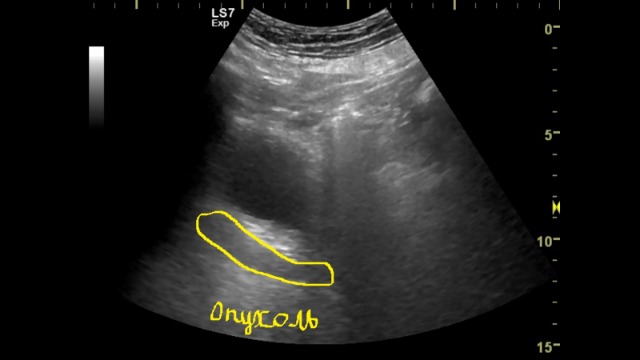

Изображение сжимается на ютубе. Я обозначил на фото области поражения. Не затронут средний отдел. Из дистального и проксимального отделов навстречу идут два очага. При цистоскопии из устья видно образование.